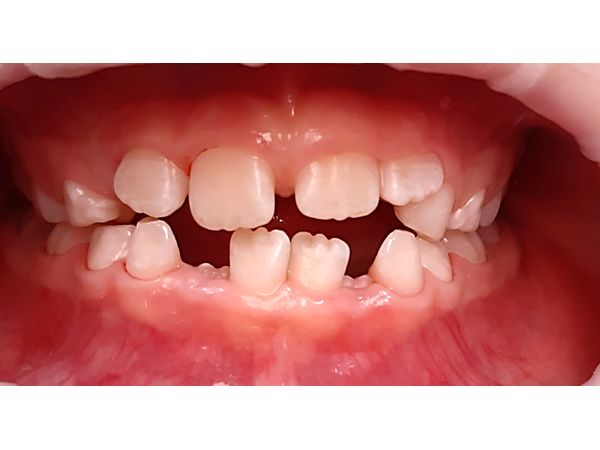

При осмотре лицо симметричное. Кожа нормального цвета. На подбородке остались царапины. Верхняя губа отекла, прощупывание вызывало боль. Рот могла открыть полностью, но закрыть не получалось из-за смыкания правых резцов снизу и сверху. Верхние правые резцы (зубы 51 и 52) располагались вне лунок, были прикреплены к десне. Подвижность III степени (шатались во все стороны). Лунки заполнены сгустками крови. Левый верхний центральный резец (зуб 61) двигался влево-вправо и вперёд-назад. Простукивание резко болезненное.

Перелом корня зуба 61, полный вывих (экзартикуляция) зубов 51 и 52.

Через два года после травмы, когда девочке исполнилось 7 лет, 61 зуб сменился на постоянный. Постоянный левый центральный резец (зуб 21) и верхние правые резцы (зубы 11 и 12) также прорезались в срок. Они росли в правильном положении, без видимых патологических изменений.